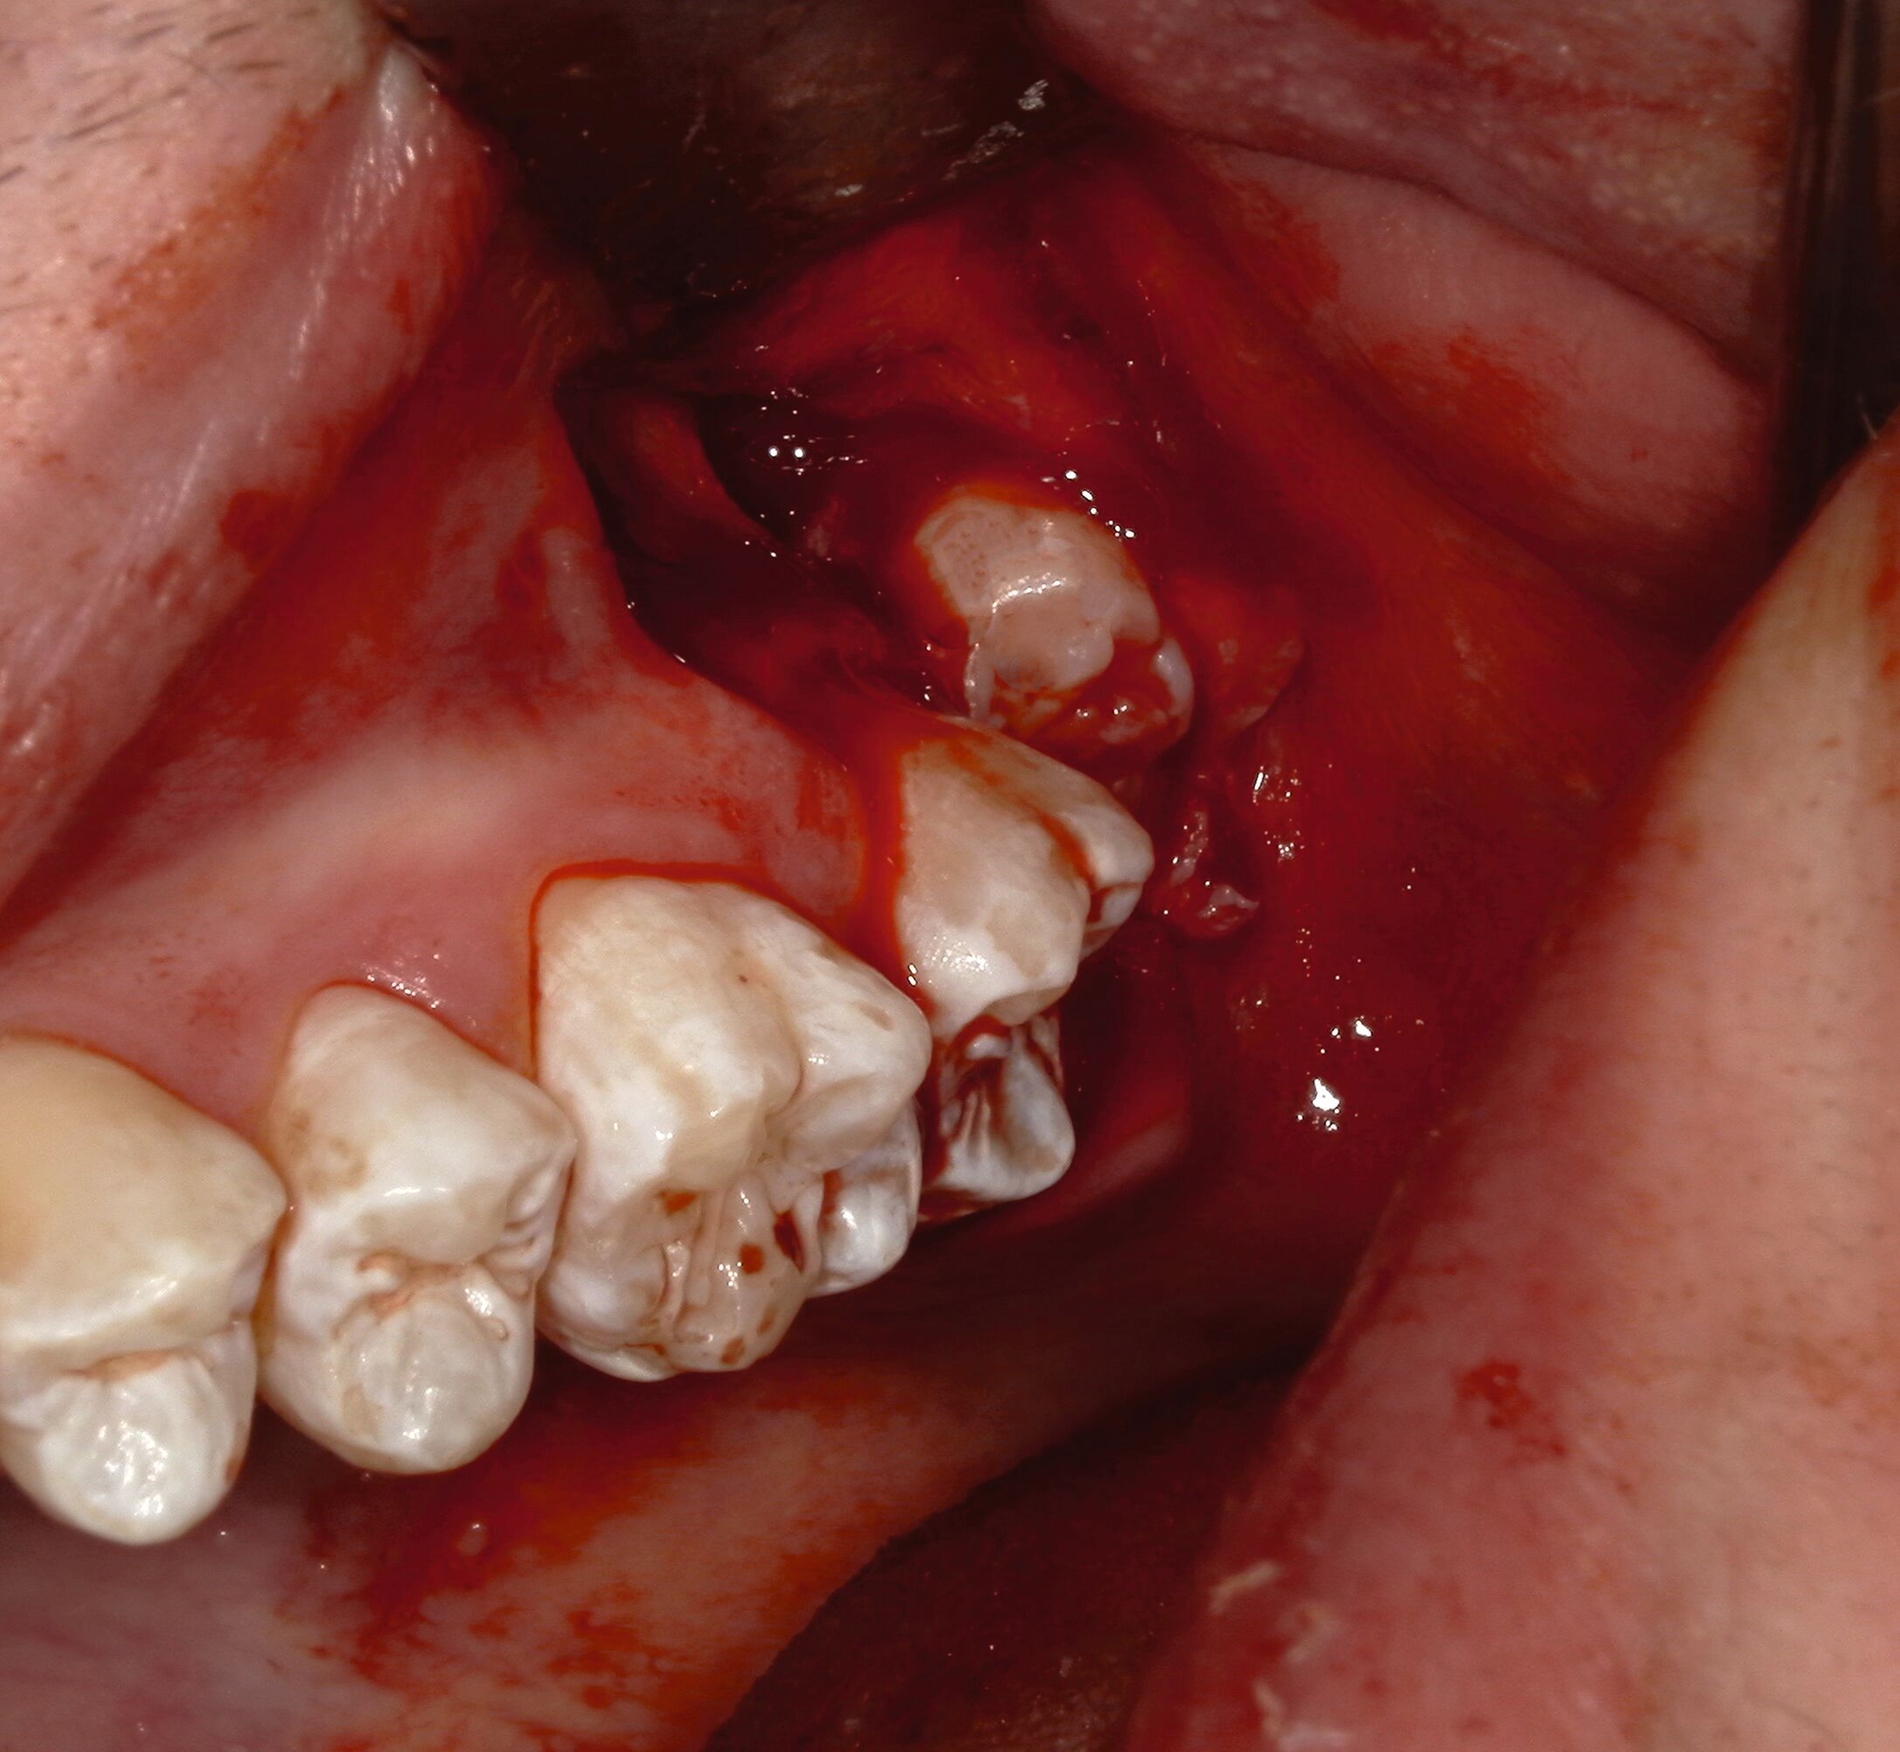

Zur Bildung eines Mukoperiostlappens wird die Gingiva anschließend vorsichtig mithilfe eines Raspatoriums präpariert. Falls nötig kann eine kaustische Blutstillung durchgeführt werden. Neben Horizontallappen (Envelope-Lappen) können auch trianguläre beziehungsweise Dreiecklappen angelegt werden.

Nach Freilegung des Knochens kann ein Wundhaken nach Langenbeck eingesetzt werden sowie ein Bohr-Raspatorium zum Schutz des N. lingualis subperiostal lingual [Gutwald et al., 2019]. Unter Verwendung eines rotierenden Instruments (Kugel- und Lindemann-Fräse) oder Piezochirurgie wird der Knochen im Bereich der Zahnkrone abgetragen und diese freigelegt (Abbildung 8). Danach kann der Weisheitszahn vorsichtig mithilfe eines Bein‘schen Hebels anluxiert oder, falls dies noch nicht gelingt, mittels einer Lindemann-Fräse geteilt werden. Dabei wird am größten Kronendurchmesser die Krone mit der Fräse abgetrennt und die Wurzel anschließend separat entfernt (Abbildungen 9 und 10) [Gutwald et al., 2019; Schwenzer, 2019].